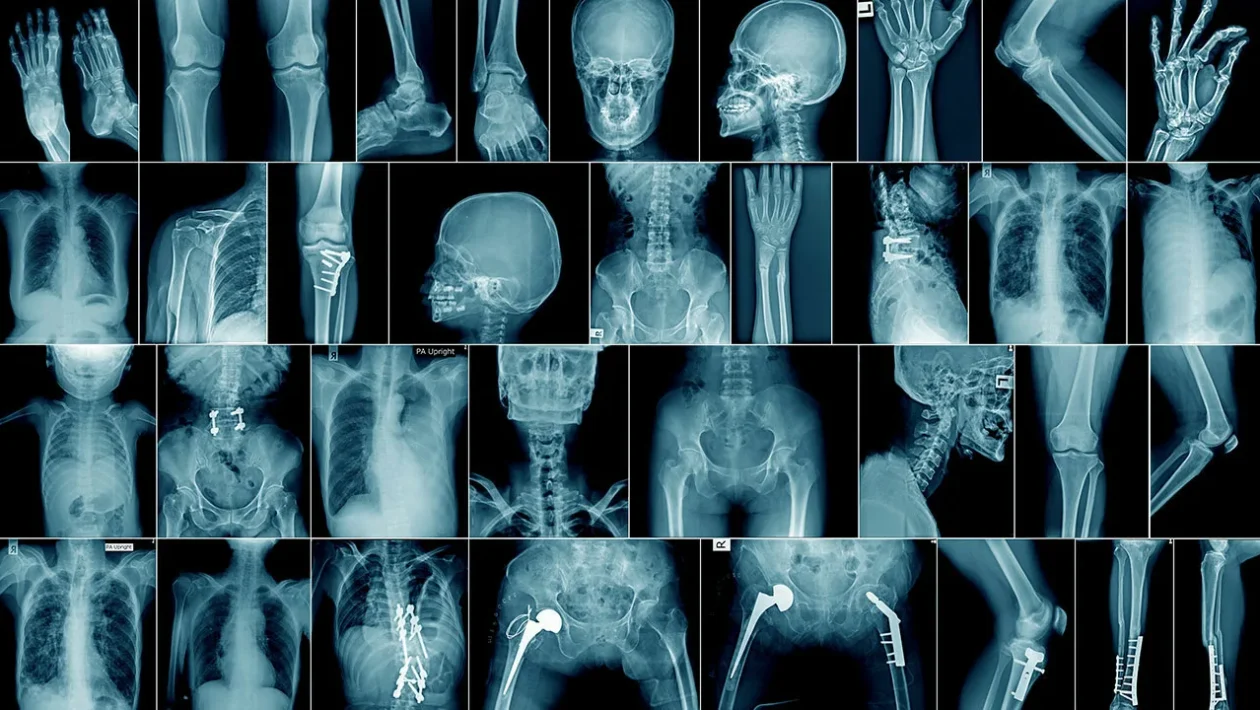

Tämä infektio voi vaikuttaa mihin tahansa luuhun kehossa, vaikka useimmiten se esiintyy nikamissa ja pitkissä luissa, kuten sääriluussa, reisiluussa tai olkaluussa selitti ABC:lle tohtori José Luis del Pozo, Navarran kliinisen yliopiston (CUN) tartuntatautien ja mikrobiologian osaston johtaja.

Toinen tapa, jolla mikro-organismit pääsevät luuhun, on trauma, esimerkiksi avoin luunmurtuma tai nivelkorvausleikkauksen seuraukset.